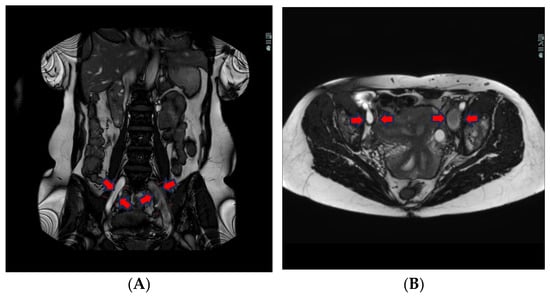

The T2-weighted (T2w) sequence shows, on the other hand, liquid blood as black and signal empty, i.e., flow void. This is due to the protons in the blood moving during the period between the excitation pulse and the measured pulse, meaning that there is not a null signal from the area where the protons were at the excitation. The protons in thrombi, on the other hand, are “locked” in the coagulated stagnant blood and, therefore, indicate a coagulated liquid, which in turn is white on a T2w sequence (Figure 2).

The T2w sequence is less sensitive to artefacts than the BFFE, which can be extremely important for patients having more DVT or being treated with stents earlier. The T2w has a better linear resolution and gives better tissue differentiation in the images (see differences between Figure 1 and Figure 2).

Figure 2. Transversal T2W imaging shows that the thrombus in the left iliac vein has a hyperintense signal because of clotted blood in the thrombi and lack of flow in the vein. The right iliac vein has a hypointense signal because the flowing blood = flow void.